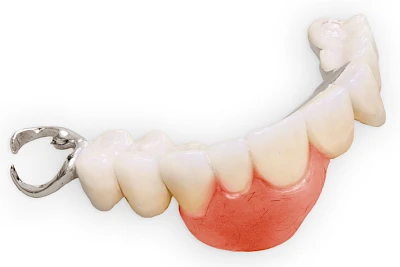

Auch wenn Zahnprothesen drücken, sollten vor allem Teilprothesen jeden Tag wenigstens für ein paar Minuten getragen werden, damit sich die eigenen Zähne nicht unbeabsichtigt verstellen und die Prothese weiter passt.

Heute werden in Deutschland Menschen mit Lippen-Kiefer-Gaumenspalten bereits ab Geburt von Experten verschiedener Fachrichtungen (Mund-Kiefer-Gesichtschirurgen, Kieferorthopäden, Logopäden) betreut, damit entsprechende Korrekturen schon frühzeitig erfolgen können. Gerade jedoch bei älteren Menschen ist dies nicht immer geschehen. Diese Menschen tragen häufig technisch aufwendige Zahnprothesen.